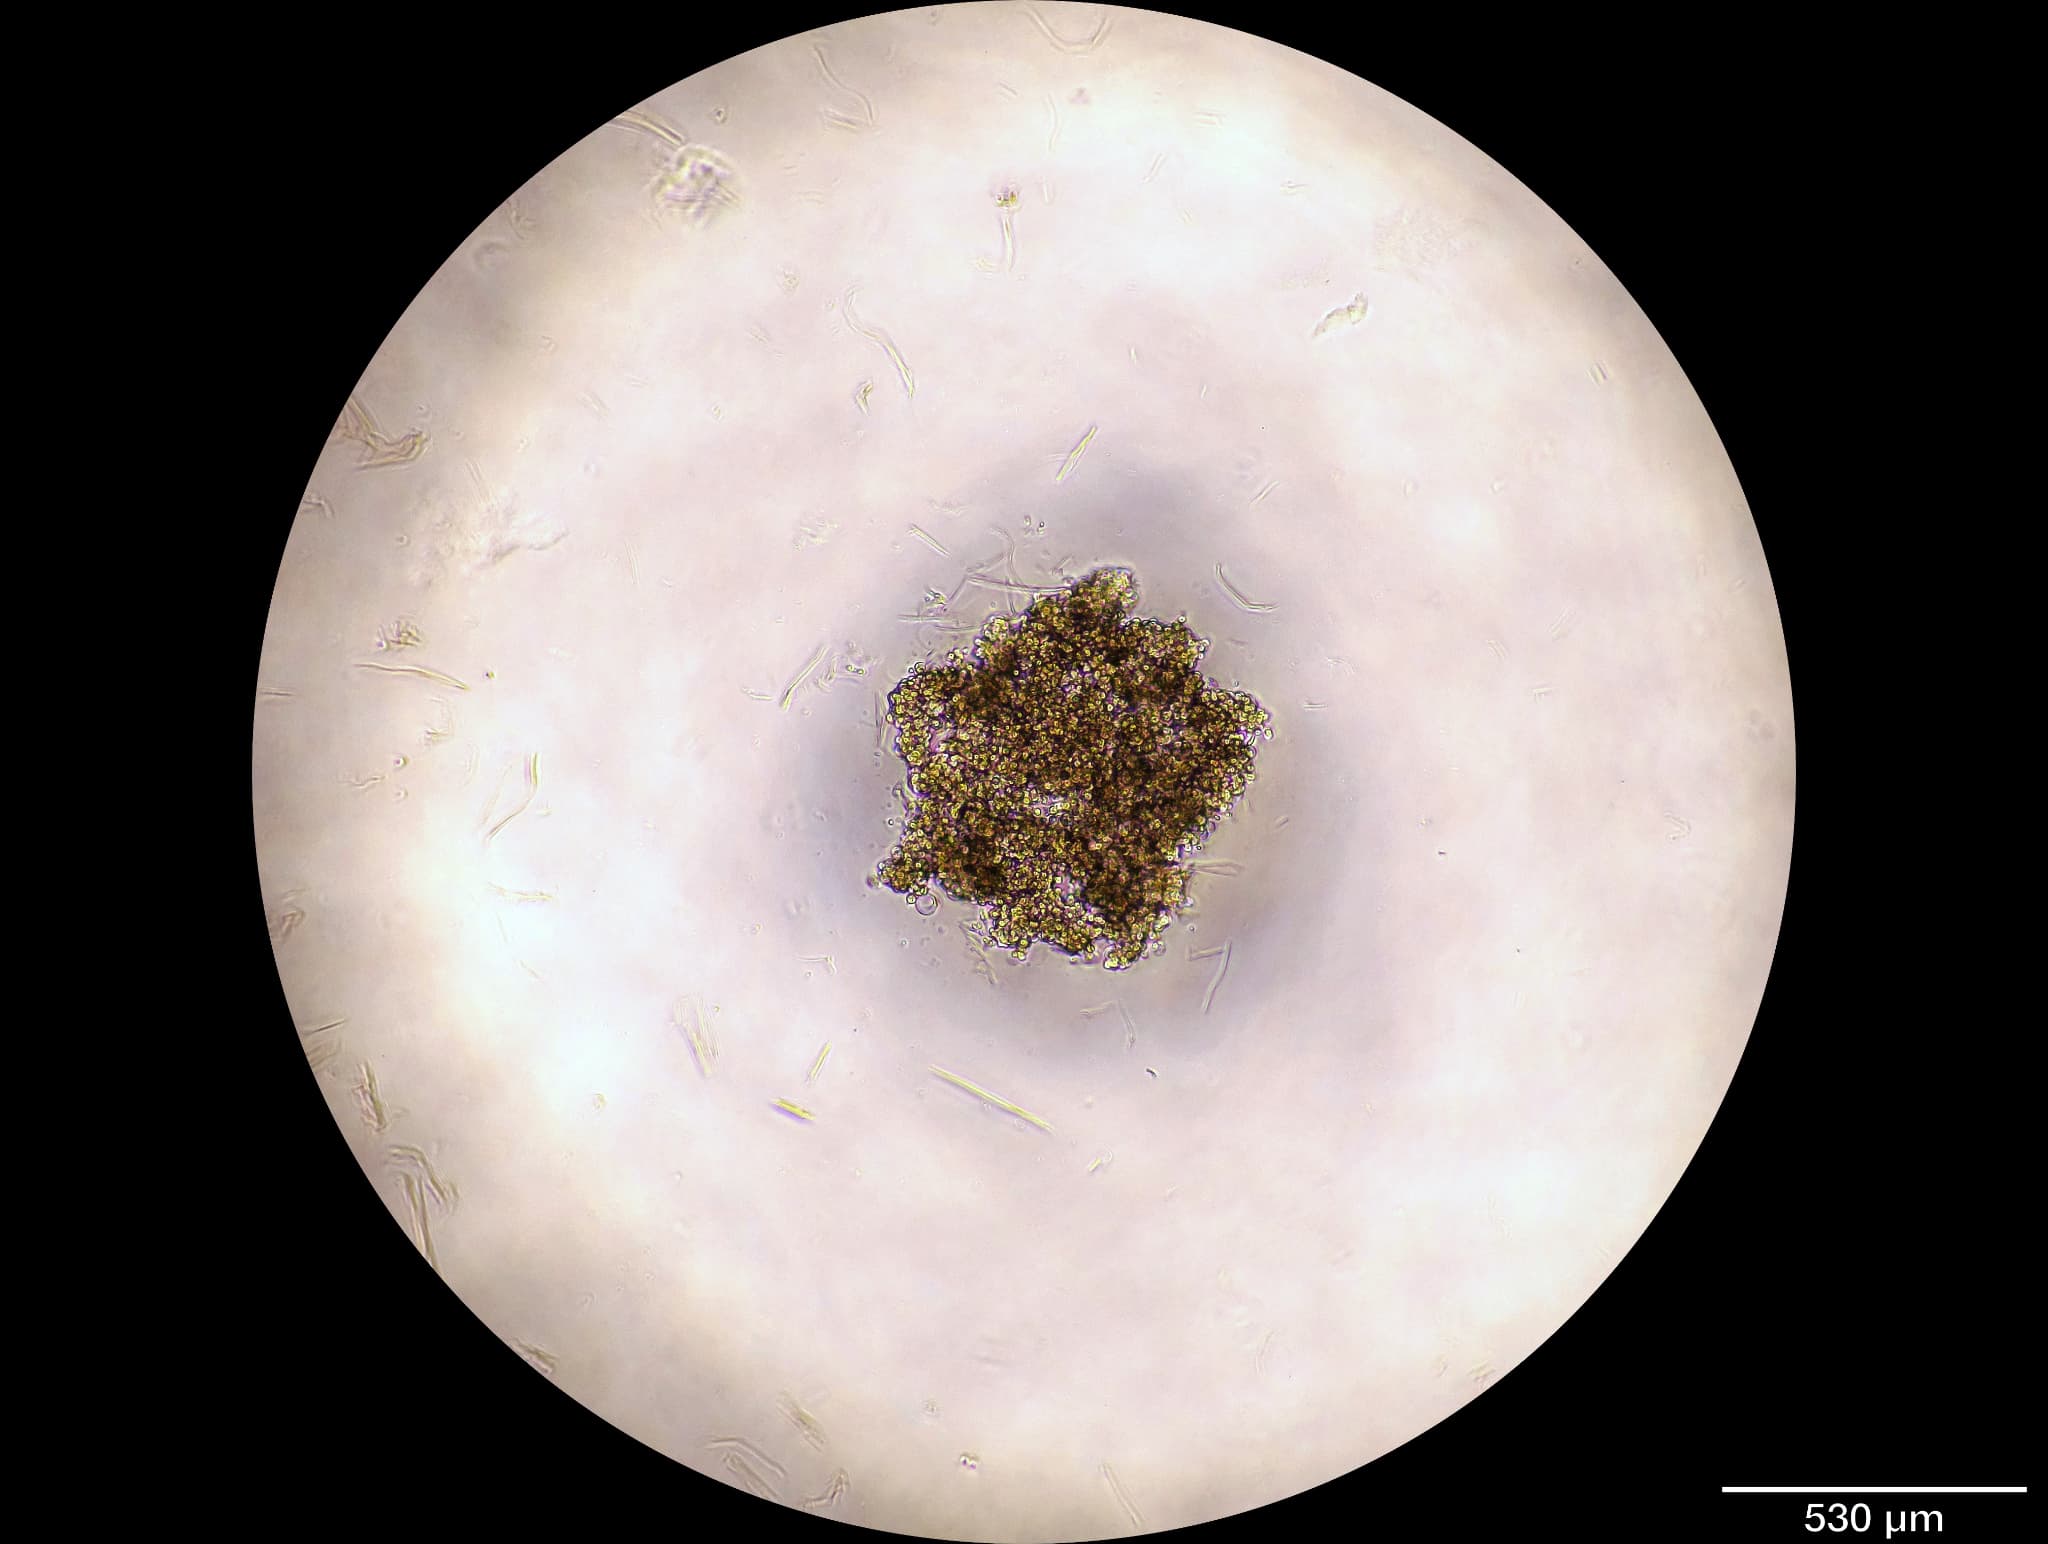

ヒトがん細胞スフェロイド(三次元培養)を用いて、化合物の生物活性を評価しています。スフェロイドは厚みがあるため撮影設定に習熟が必要ですが、Rebelの自動調整機能により短時間で適切な画像を取得できました。正立・倒立の両観察が容易で、上面と底面の同時観察にも有用でした。

| 検体・サンプル: | ヒト卵巣がん由来細胞(OVCAR-3) |

| 詳細: | 96ウェルプレートで培養したOVCAR-3細胞のスフェロイド |

| 顕微鏡: | 倒立顕微鏡 |

| 対物レンズ: | 4X Plan Achromat Phase, 0.17 | N.A. 0.13 | WD 17mm |

| 消耗品: | 96ウェル平底プレート |

| 補足: | ウェル内でスフェロイドが形成された後の画像 |